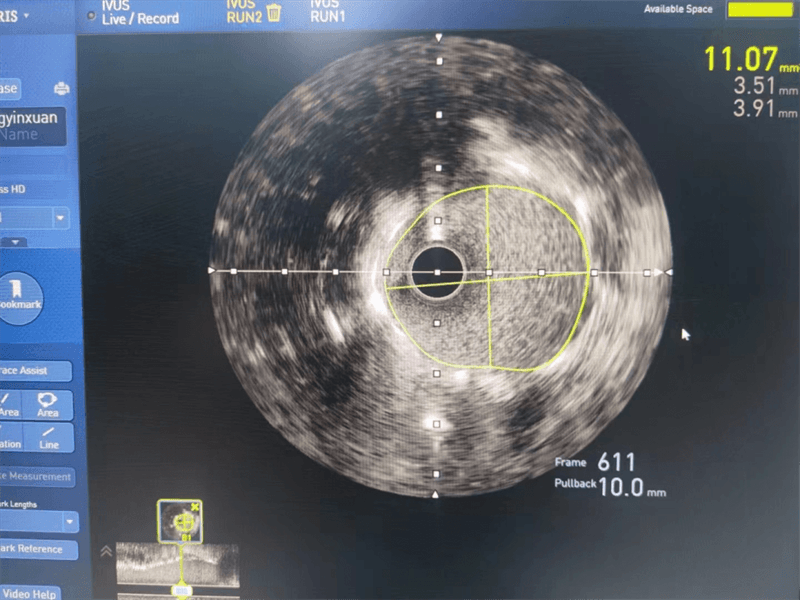

与患者家属沟通后,其女儿犹豫不决、忧心忡忡,经过崔主任认真分析病情、充分沟通,征得患者及家属同意后,为安全、精准处理病变,选择进行血管内超声检查,经血管内超声检查提示左主干至前降支近段纤维斑块,球囊扩张后面积3.97mm2,斑块负荷70%,回旋支近段中度狭窄,斑块负荷较轻。